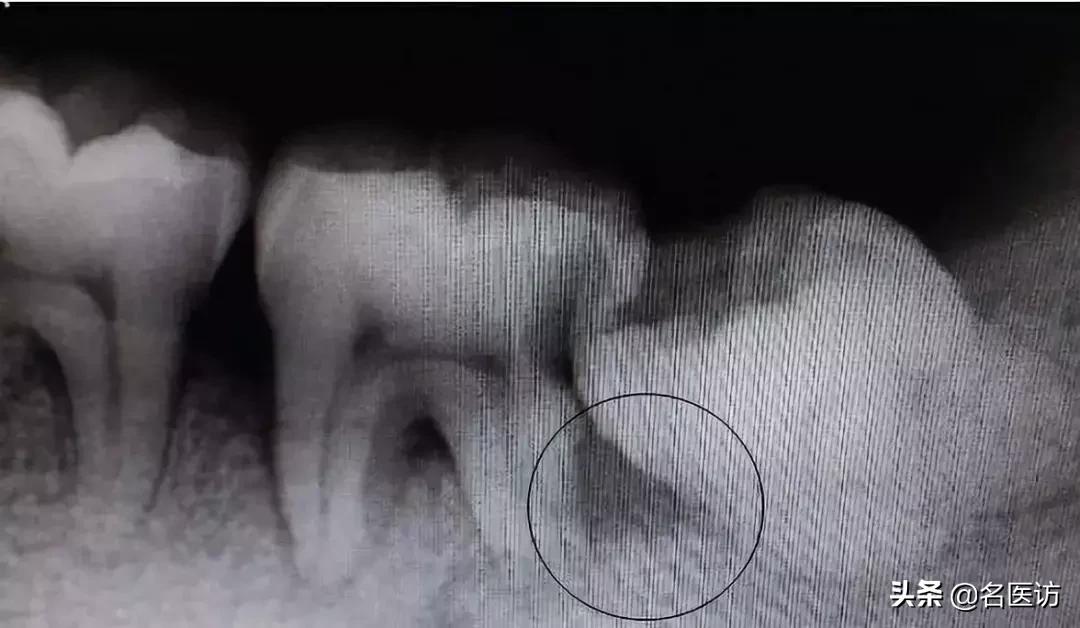

智齿以及前面的第二磨牙龋坏

第二磨牙与智齿之间牙槽骨吸收